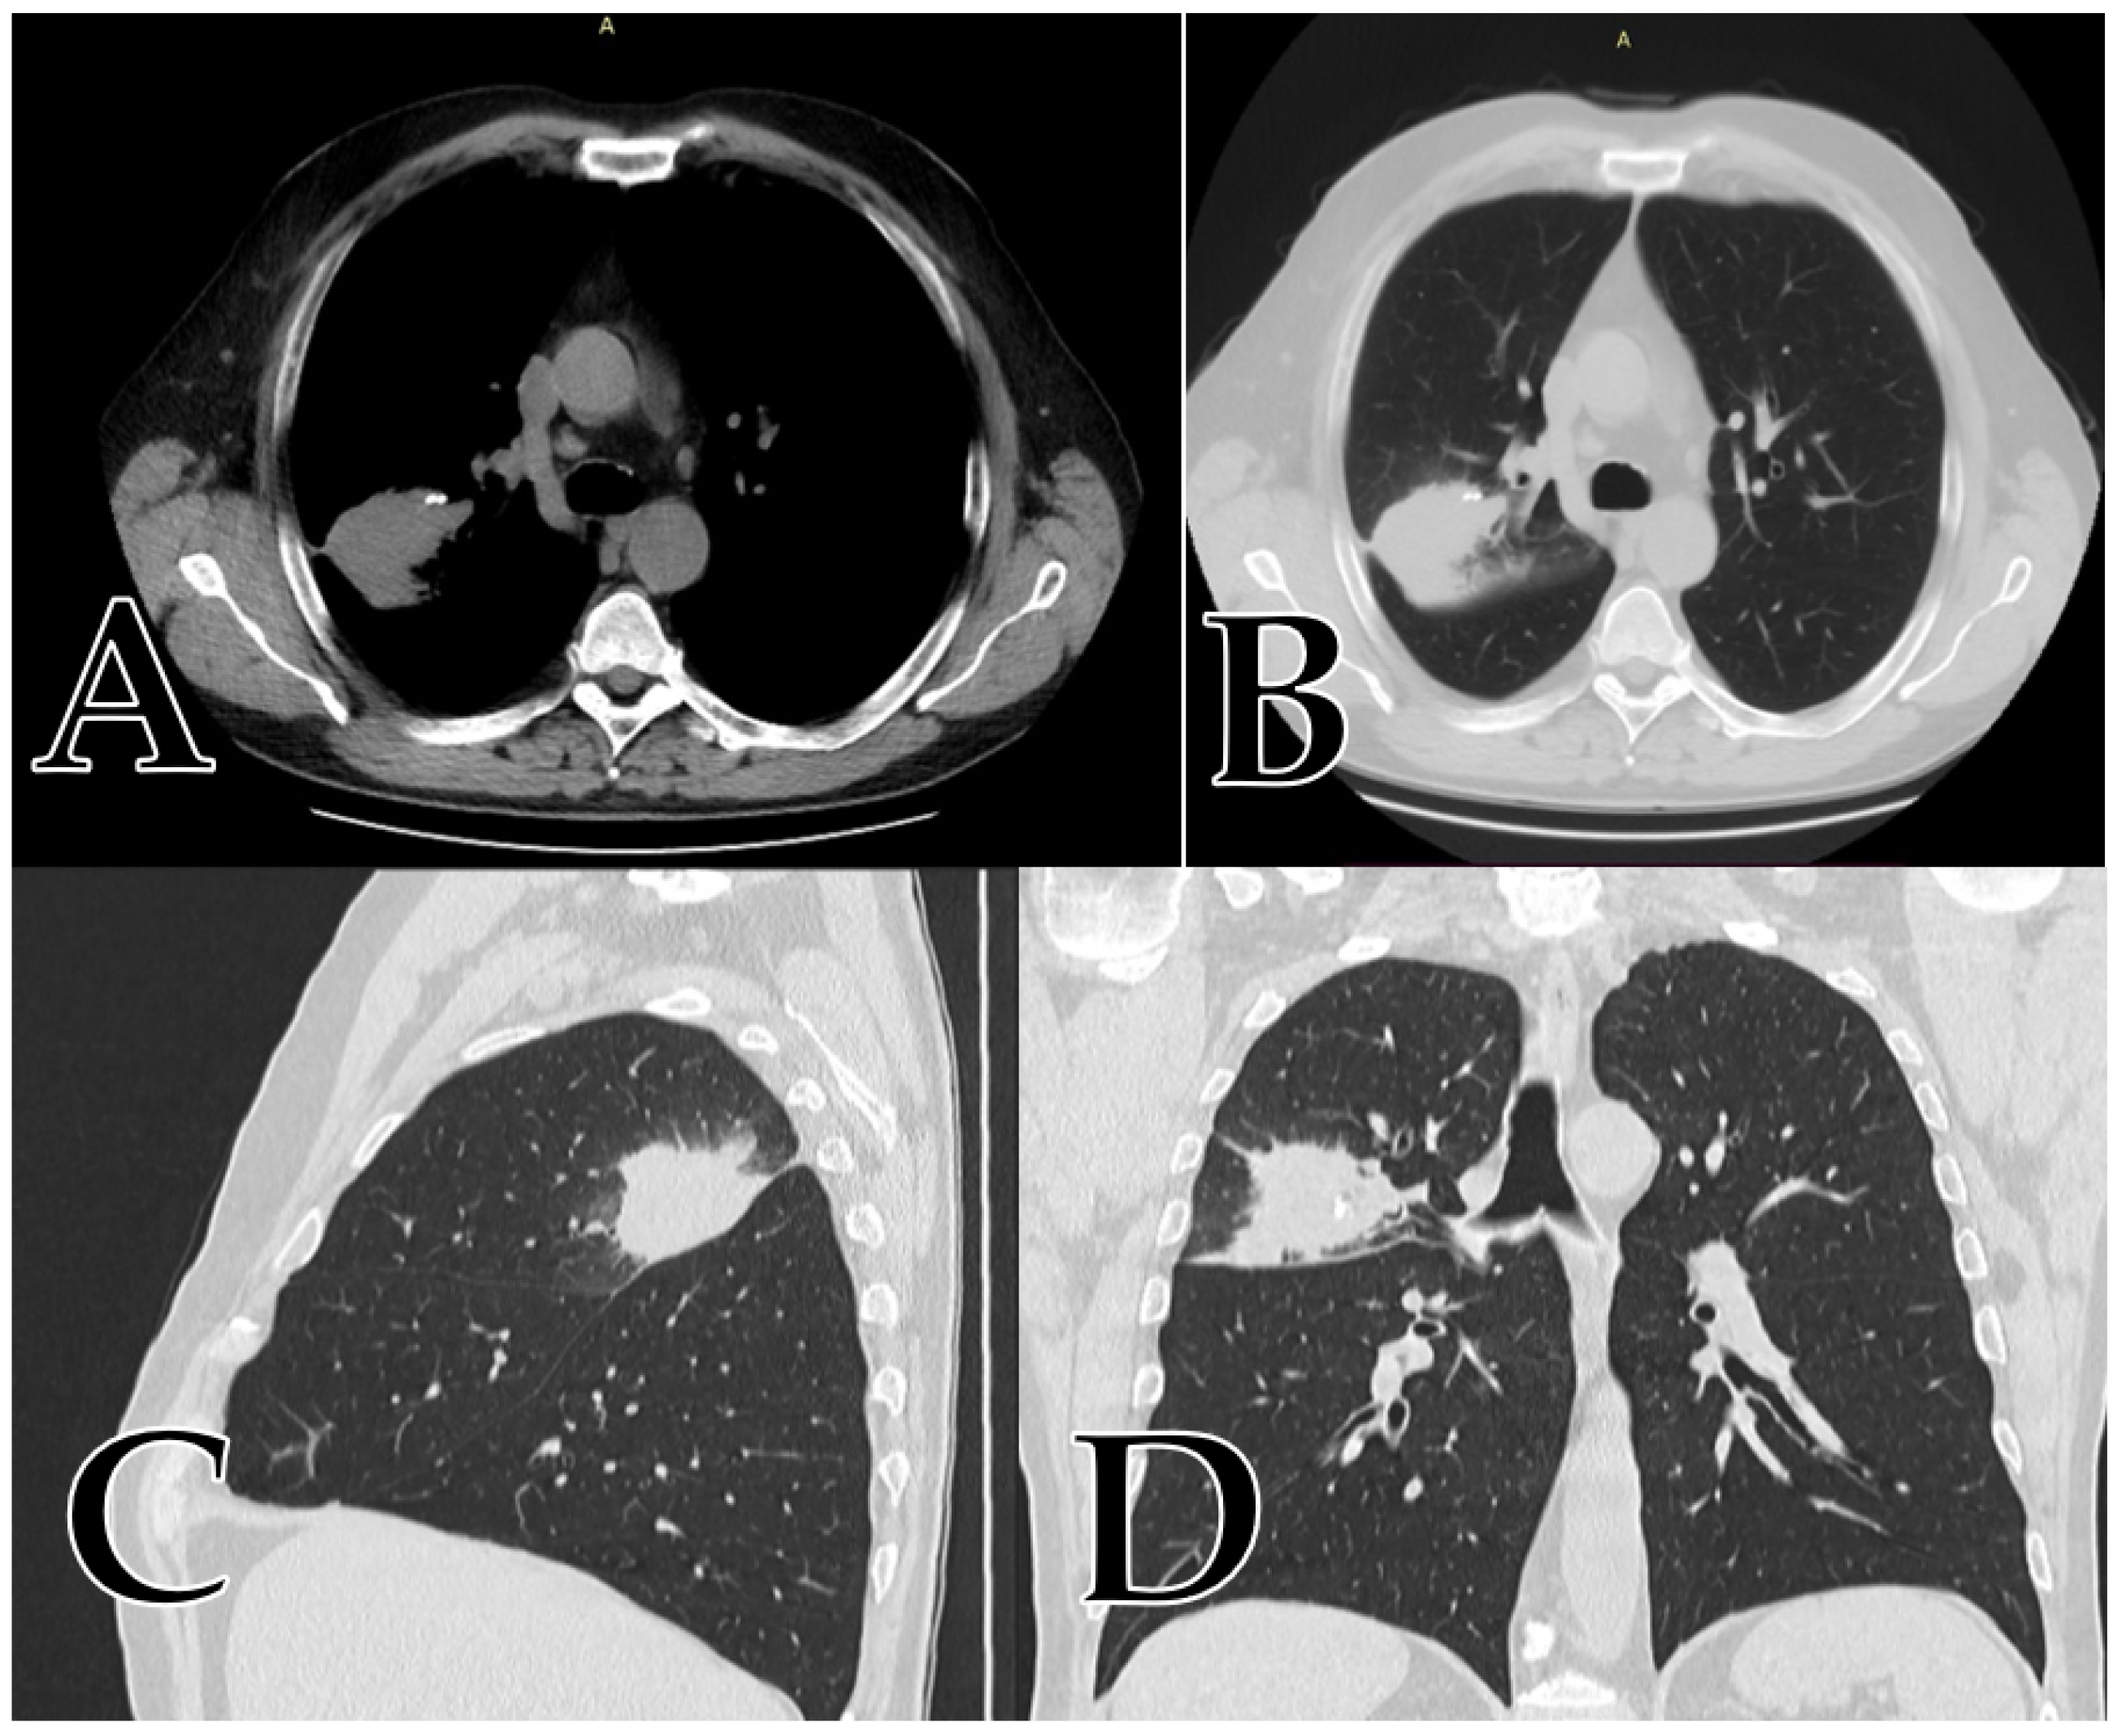

At the time of admission, the patient’s general status was worse, having symptoms such as a productive cough, fatigue, and dyspnea. The CT scan showed an increase in the diameter of the mass by 5 cm, having all the characteristics of a malignant lung tumor (Figure 3A–D), just as we described them for our study, see Figure 3 below.

Figure 3.

(A,B) coronal view; (C) sagittal view; (D) axial view of a right upper lobe mass presenting all the aspects of malignancy: size over 5 cm, gross spiculation, attenuation alternances (part solid, part GGO), punctuate calcification, no tumoral fatty tissue, positive bronchial sign with a mean value of 34 HU and a growth rate of 5 cm over 6 months period.